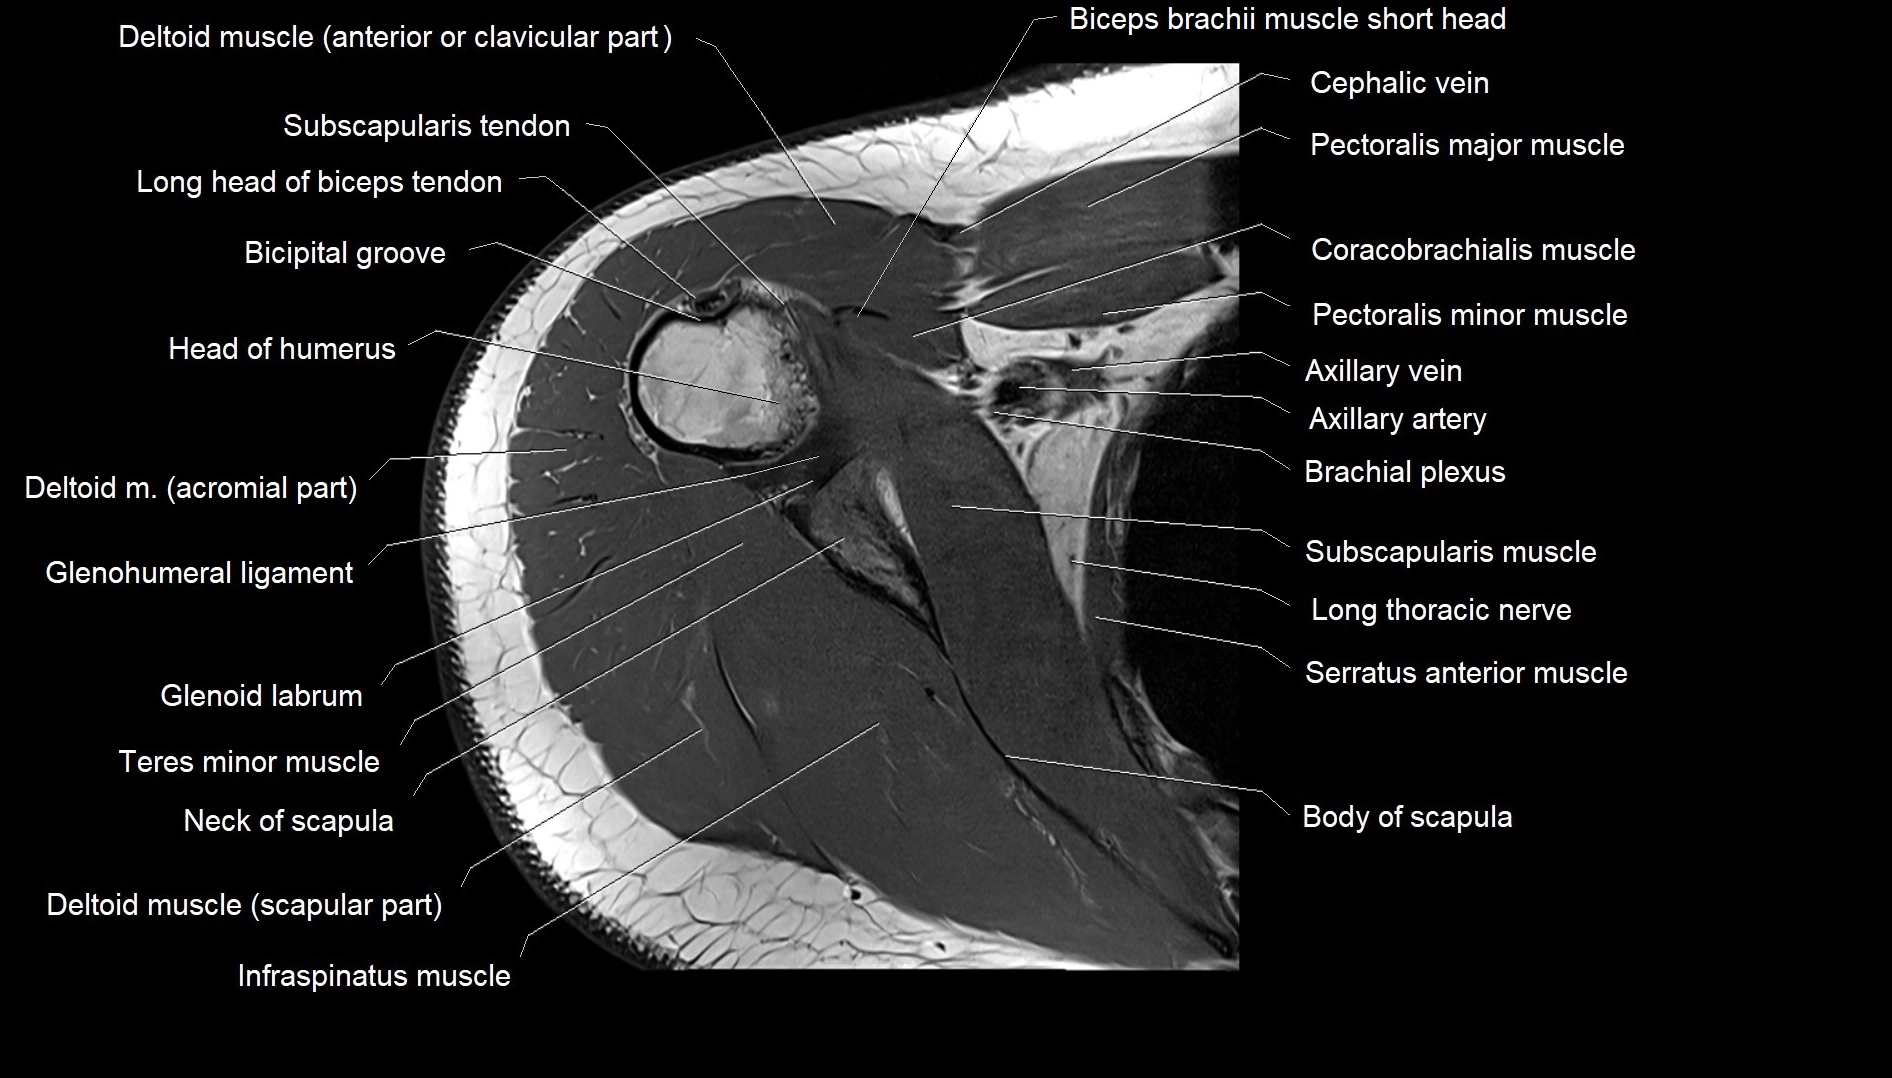

TEST YOURSELF

Fullscreen Image